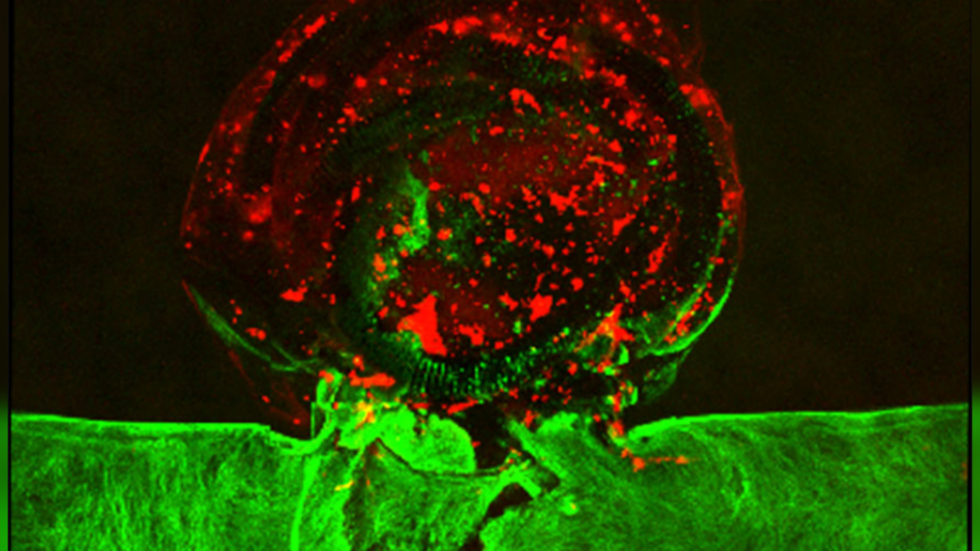

Struktura në formë aneurizmi e shtypur në 3D është bërë nga hidroxheli në të cilën futen qelizat e trurit njerëzor të quajtur hCMEC, të cilat më pas përhapen dhe veshin muret e strukturës, duke krijuar një aneurizëm ‘të gjallë’ që u lejon mjekëve të ekzaminojnë dhe të punojnë.